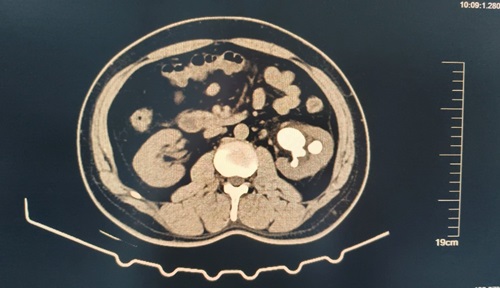

患者,男,61歲,主因“發(fā)現(xiàn)左腎鹿角形結(jié)石1月余”入院。泌尿系CT顯示:左腎鹿角狀結(jié)石;右腎結(jié)石。后在可控負(fù)壓吸引下行輸尿管軟鏡鈥激光碎石術(shù)治療腎結(jié)石。

術(shù)前示圖如下:

術(shù)后6周復(fù)查泌尿系CT,左輸尿管內(nèi)支架置入術(shù)后,左腎結(jié)石基本消失。

術(shù)后6周復(fù)查泌尿系CT,左輸尿管內(nèi)支架置入術(shù)后,左腎結(jié)石基本消失